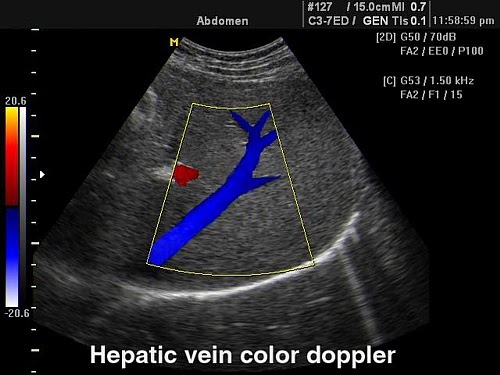

Flow - цветной допплер - ЦДК. Учитывает приближающийся и удаляющийся кровоток, применяется для исследования кровотока в сосудах, в эхокардиографии. В сочетании с энергетическим допплером помогает в дифференциации кист и опухолей.

PowerFlow - энергетический допплер. Окрашивает изображение в зависимости от интенсивности допплеровского сигнала.

Directional PowerFlow - направленный энергетический допплер. Добавляет цвета в режиме Power Flow. Применяется при исследовании сети мелких сосудов (щитовидная железа, почки, яичник), вен (печень, яички) и др. Более чувствителен к наличию кровотока, чем цветовой допплер.

Дуплексные и триплексные режимы (B+Color+D)

Дуплексный режим позволяет выявлять патологии каналов, нарушение их функций.

На его основе можно сделать вывод о строении вен и артерий, степени их сужения, выявлять патологии в строении сосудистой системы, поставить точный диагноз.

Триплексный режим расширяет возможности дуплексного. Добавляет режимы цветного допплера, по которым можно наглядно судить о направлении кровотока и его скорости, Также позволяет более точно оценить проходимость сосудов и степень стеноза.